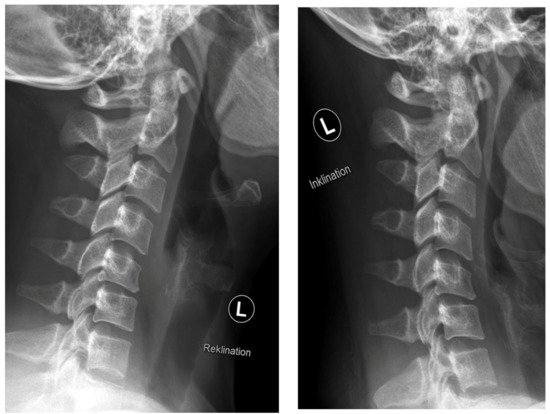

Figure 2.

Preoperative radiographs in flexion (“Inklination”) and extension (“Reklination”).